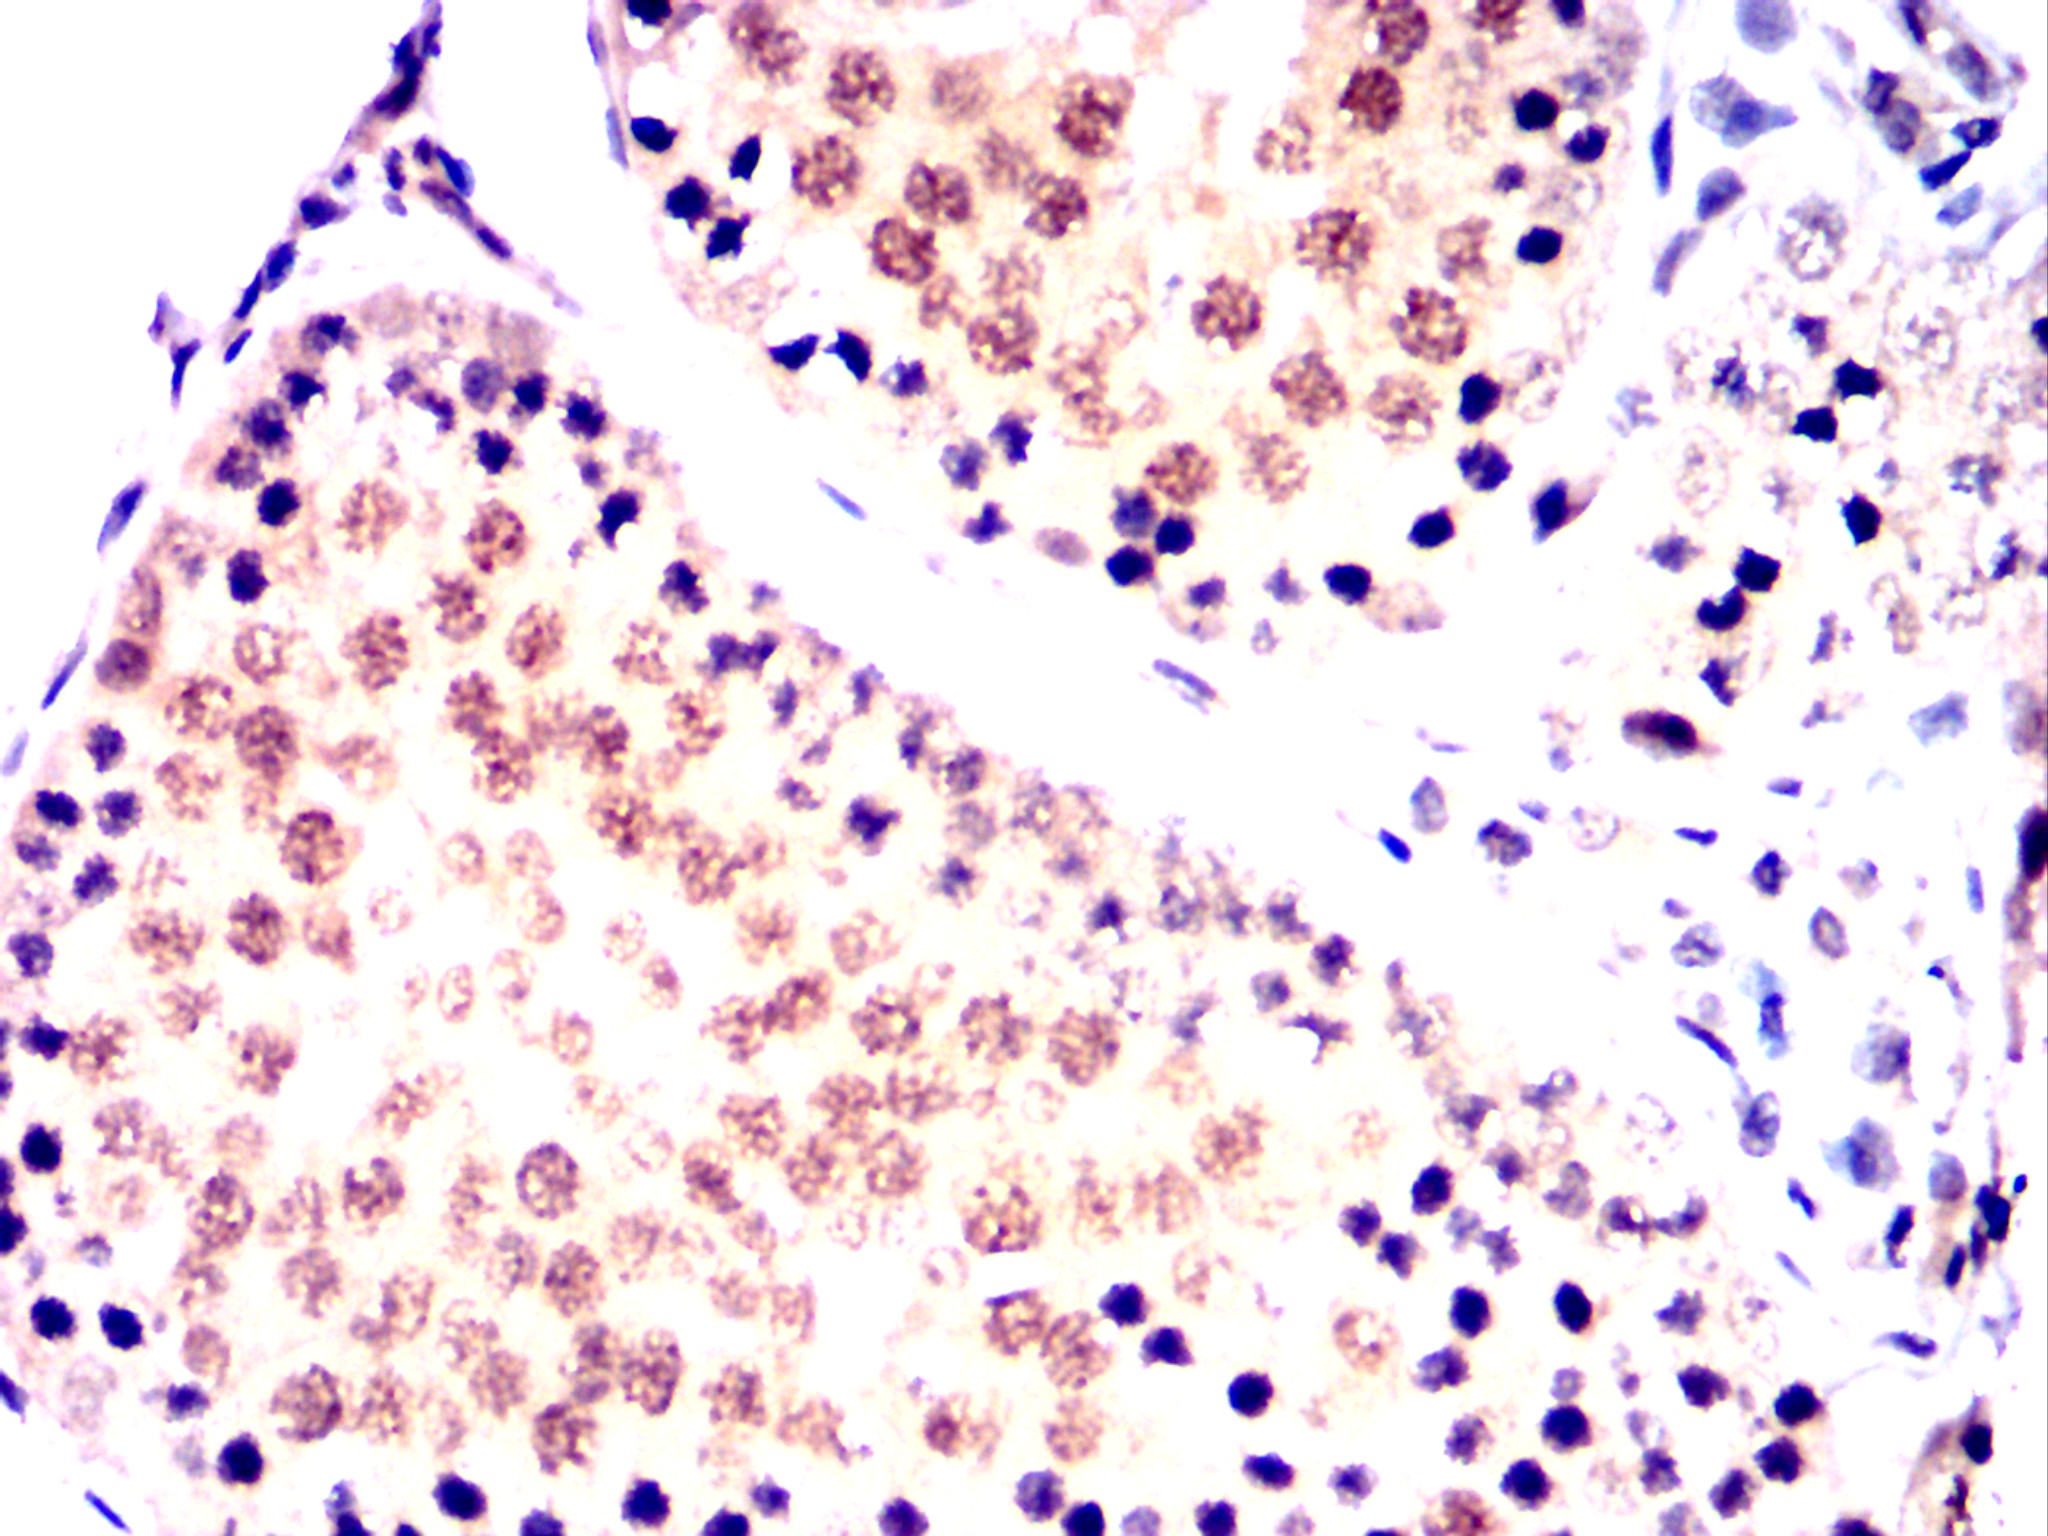

Immunohistochemical analysis of paraffin-embedded human prostate tissues (left) and colon cancer tissues (right) using OTX2 mouse mAb with DAB staining.

Immunohistochemical analysis of paraffin-embedded Mouse testis using OTX2 mouse mAb with DAB staining.